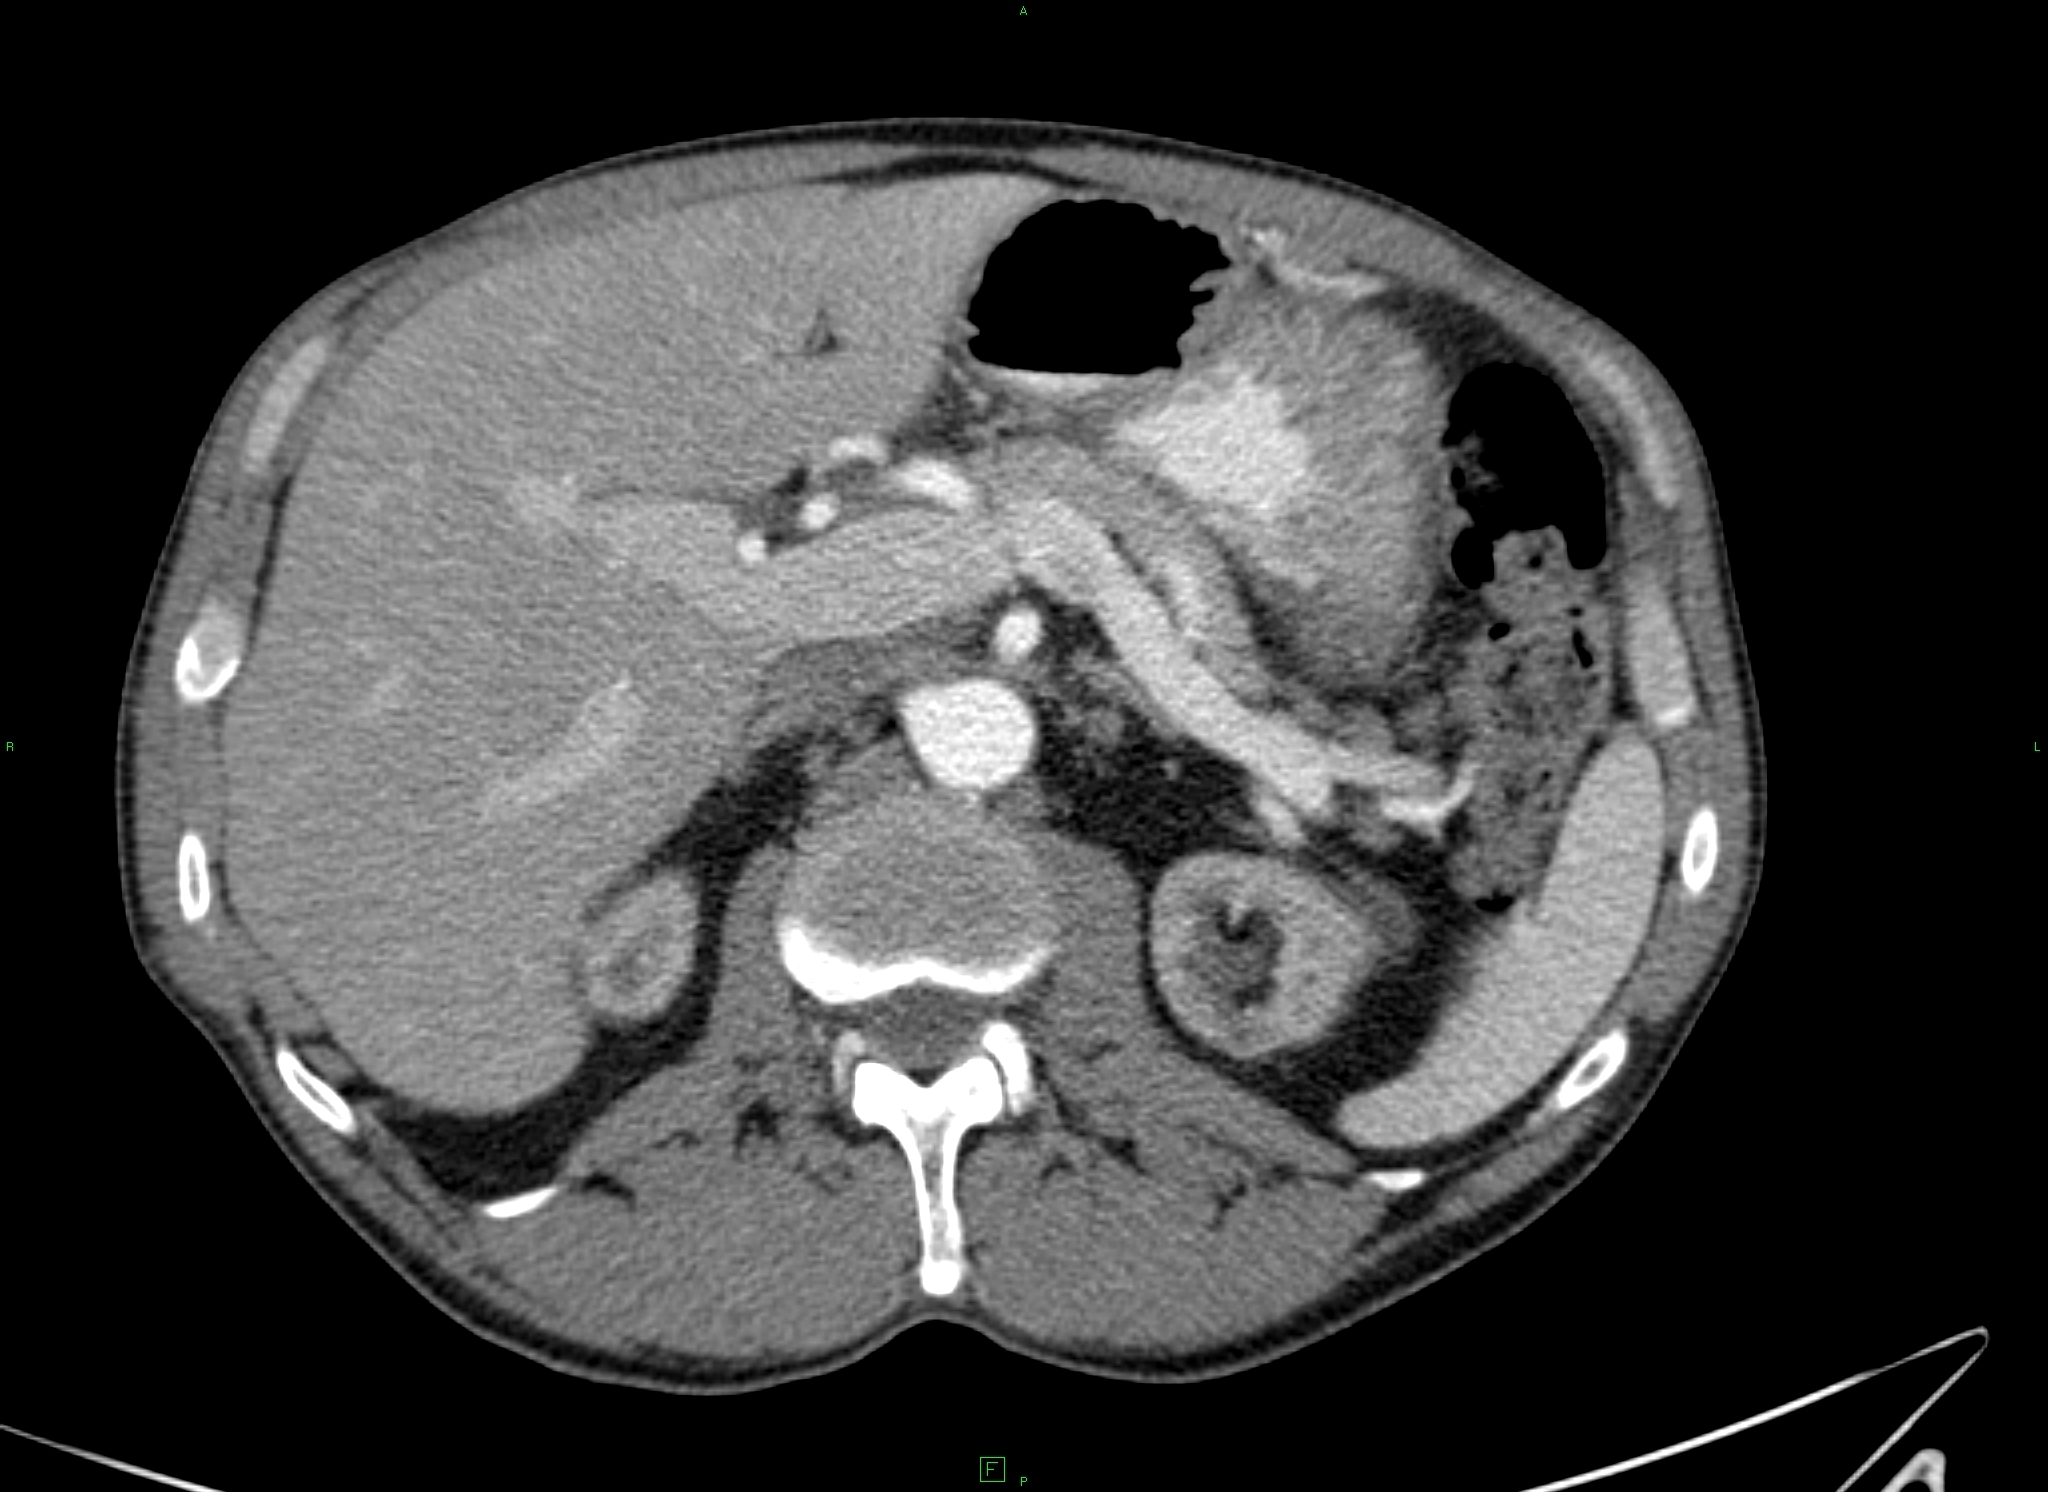

14.1.1.3. CT

Nowadays, CT is a basically important method amongst the modern diagnostic imaging services. (Figure 4) By the application of the multidetector CTs a chance is given to perform multiphase (without contrast, arterial, portal and late phase) CT scans, which provide important additional information because of the different hemodynamics of certain intrahepatic nodules. Multiplanar (sagittal, coronal, oblique) and 3D reconstructions can be adopted from the axial plane CT slices. Due to CT angiographic techniques, excellent spatial resolutional 3D reconstructional images can be performed both on the arterial (hepatic artery) and the venous sides (portal vein, hepatic veins, collateral veins in case of portal hypertension, CT control of transjugular portosystemic shunts)..

Figure 4. Liver, contrast enhanced CT, venous phase